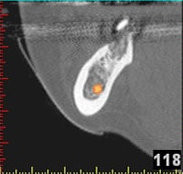

3D-Implantatplanung - Detailaufnahme 1

3D-Implantatplanung - Detailaufnahme 2

3D-Implantatplanung - Detailaufnahme 3

3D-Implantatplanung - Detailaufnahme 4

3D-Implantatplanung - Detailaufnahme 5

3D-Implantatplanung - Detailaufnahme 6

3D-Implantatplanung - Detailaufnahme 7

3D-Implantatplanung - Detailaufnahme 8

3D-Implantatplanung - Detailaufnahme 9